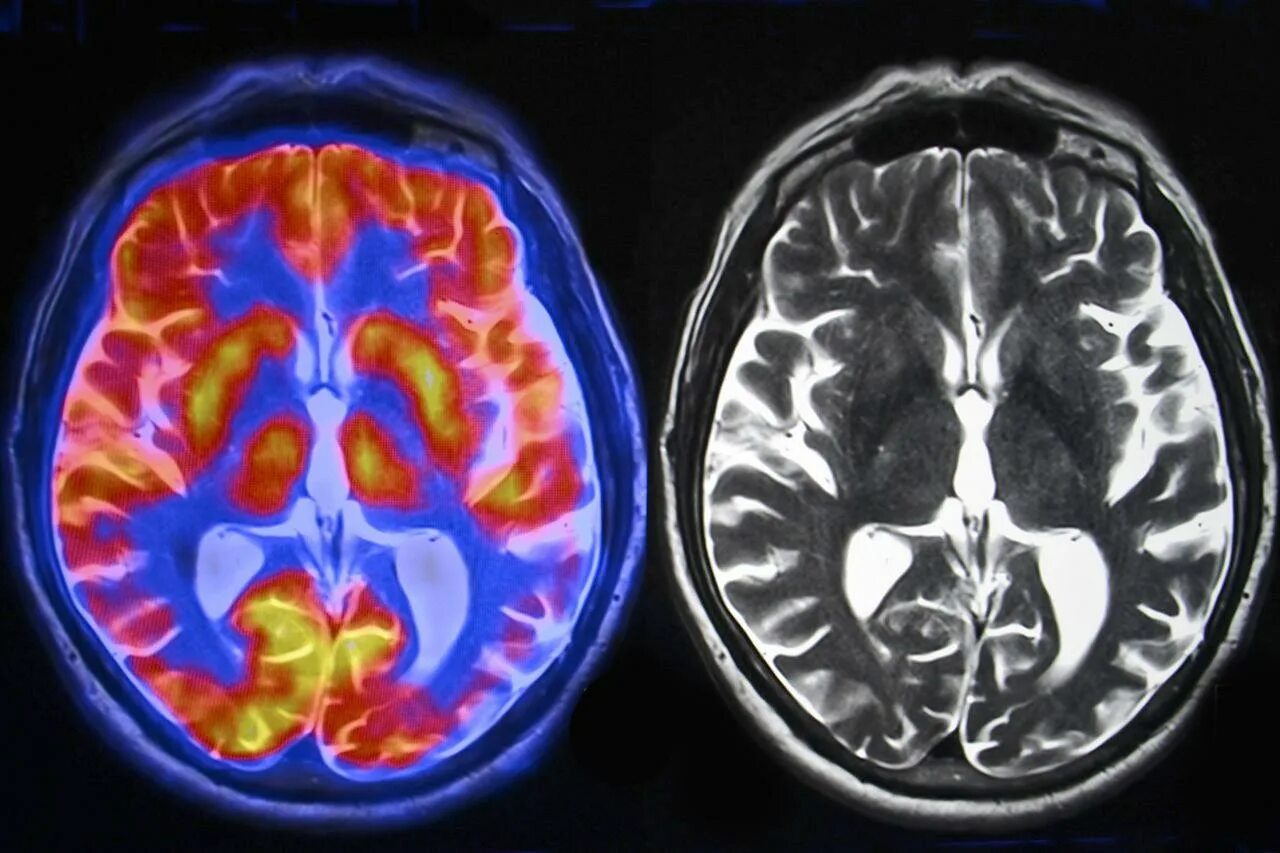

После мрт головного мозга